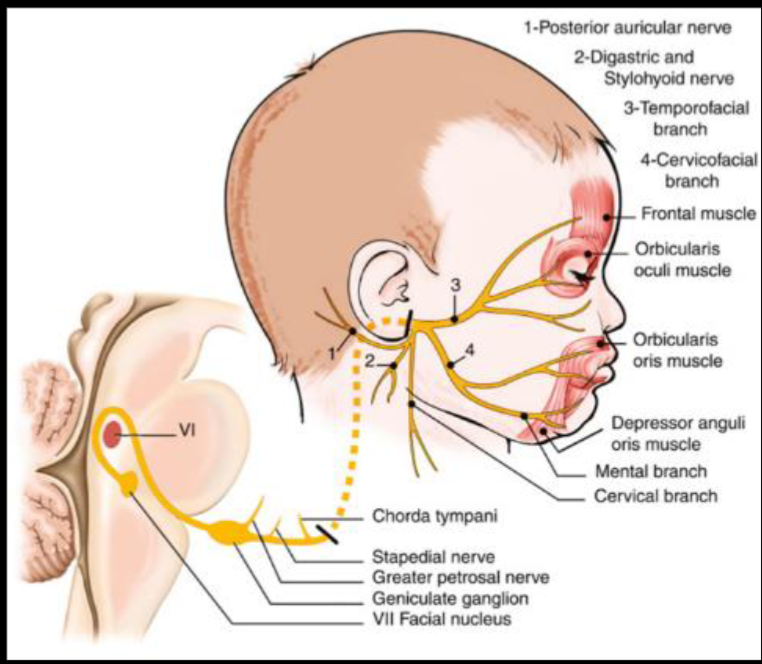

⑦: Sensory; Tast ant ⅔, sound sensitivity | Motor; Eye clos, Mouth close, blow, whistle, smile

- Facial Nerve; Keep eyes closed against resistance, blow cheeks, show teeth

CN VII - Facial Nerve

in middle ear gives two branches to chorda tympani & Stapedius (ear distrubance)

Innervations - External acoustic meatus - for sensation of ear - Motor - Movement of the face - Sternomastoid - branches nerve to stapedius - Loud sounds middle ear - & nerve to chorda tympani - Parasympathatic Submandibular & Sublingual gland

Tests

- Temporalis - raise eye brows (dont use hands )

- Orbicularis Oculi - check for resistance when eyes close

- Buccinator - Blow (palpate)

- Levator Anguli Superioris - smile

- Orbicularis Oris - whistle

- Taste anterior 2/3

UMN Palsy - Causes Includes; (hyperreflexia)

- Eyebrow raise is normal - if botox, contraindicated for the test

LMN Palsy - Causes includes

- Eyebrow doesn’t raise compared to contra-lateral